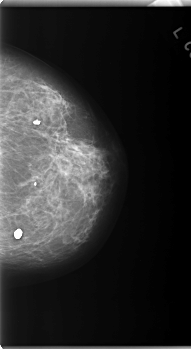

C_0171_1.LEFT_MLO

C_0171_1.LEFT_CC

LEFT_CC LINES 5928 PIXELS_PER_LINE 3240 BITS_PER_PIXEL 12 RESOLUTION 50 NON_OVERLAY